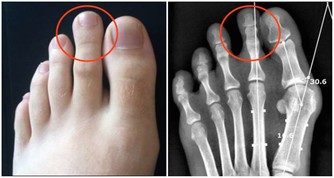

輕微缺乏維生素B2人體不會有任何感覺,但到一定程度時就會出現明顯的癥狀,首先,在人體最薄弱的地方,通常是消化道的首尾兩端,即口腔或肛門的局部,出現充血、腫脹,隨後皮膚或粘膜出現潰瘍,然後開始出血,這即是口腔潰瘍和痔瘡。如果長期缺乏維生素B2,那麼人體其它部位也會出現同樣的癥狀。

主要原因在於血管,構成血管壁的細胞離不開維生素B2,當缺乏維生素B2時,血管壁(主要是毛細血管,管壁本身就很薄)開始變薄,在血壓的作用下,血管開始向外凸起,當局部的血管都開始鼓起時,就形成了腫塊,最後血管開始裂開出血,如果發生在腦部,你猜到了嗎?對,這就是腦溢血。